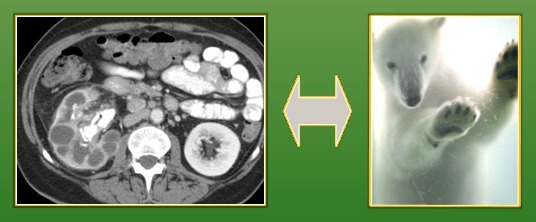

Bear paw sign: dilated calyces of the kidney whereas the renal pelvis is contracted, pathognomonic for xanthogranulomatous pyelonephritis